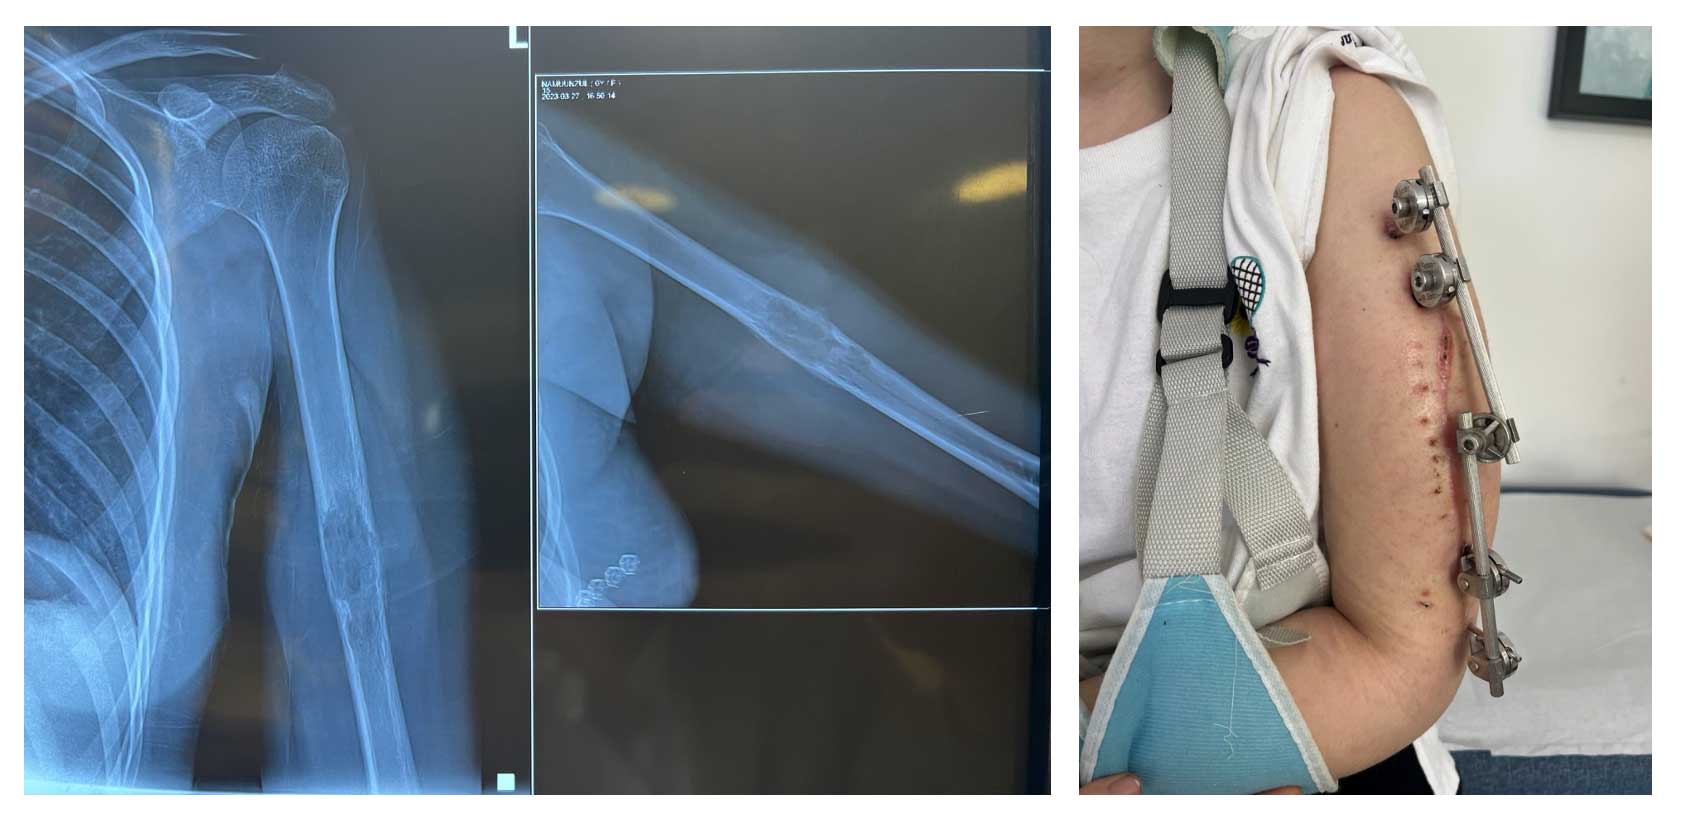

Hasta, humerus bölgesinde tümöre bağlı gelişen patolojik kırık sonrası eksternal fiksatör uygulanmış ve ameliyat sonrası radial sinir hasarına bağlı düşük el tablosu gelişmiştir. Biyopsi sonucu osteosarkom tanısı doğrulanmıştır.

Ameliyat Öncesi: Röntgende humerus orta bölgede kemik harabiyetine neden olan düzensiz kitle ve uygulanan eksternal fiksatör görülmekte.